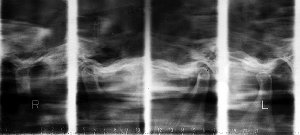

alt 図4

開口閉口時の顎関節スキャノグラム。開口時でも下顎頭は関節隆起を越えることができない。